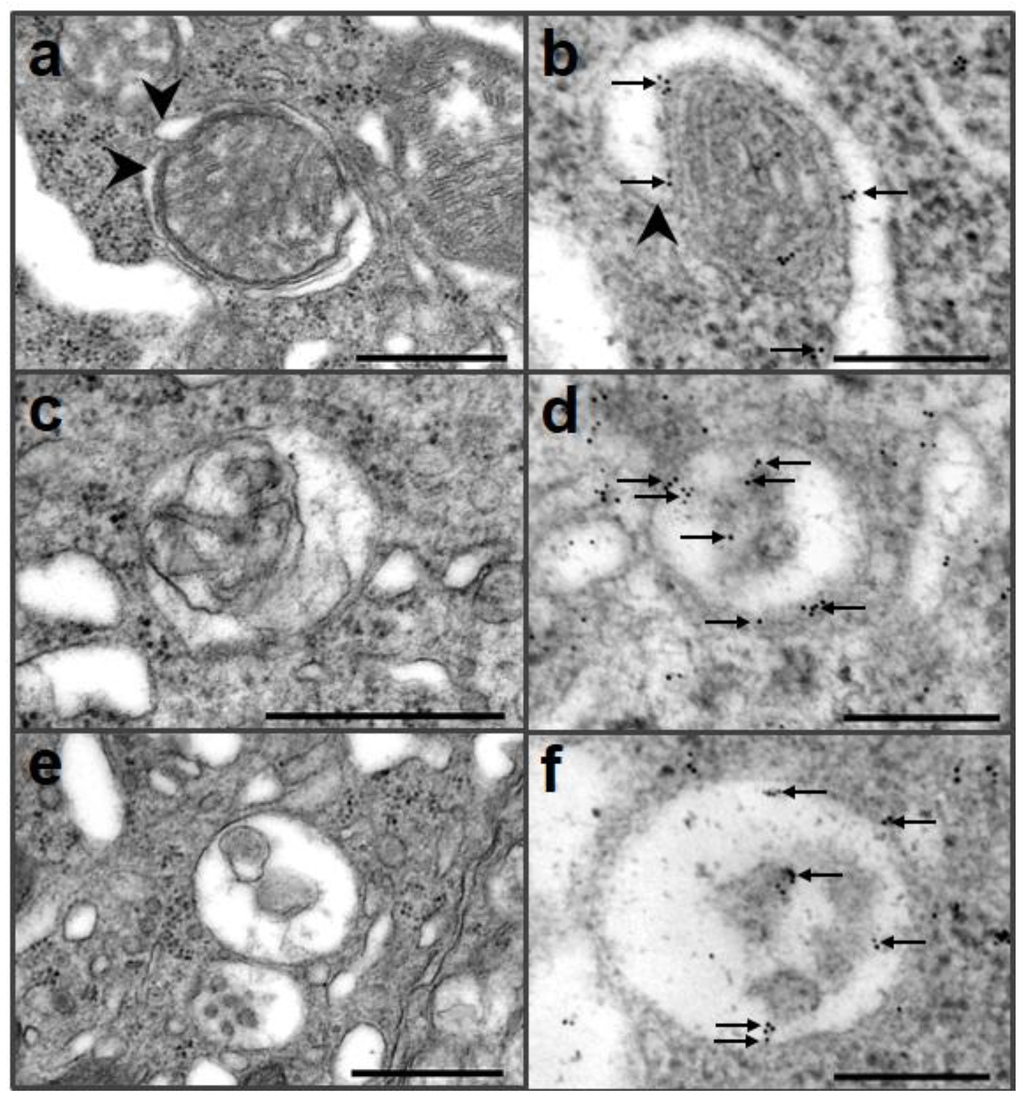

- Oh, J.M.; Shin, H.Y.; Park, S.J.; Kim, B.H.; Choi, J.K.; Choi, E.K.; Carp, R.I.; Kim, Y.S. The involvement of cellular prion protein in the autophagy pathway in neuronal cells. Mol. Cell. Neurosci. 2008, 39, 238–247. [Google Scholar] [CrossRef]

- Heitz, S.; Grant, N.J.; Bailly, Y. Doppel induces autophagic stress in prion protein-deficient Purkinje cells. Autophagy 2009, 5, 422–424. [Google Scholar] [CrossRef]

- Heitz, S.; Grant, N.J.; Leschiera, R.; Haeberlé, A.M.; Demais, V.; Bombarde, G.; Bailly, Y. Autophagy and cell death of Purkinje cells overexpressing Doppel in Ngsk Prnp-deficient mice. Brain. Pathol. 2010, 20, 119–132. [Google Scholar] [CrossRef]